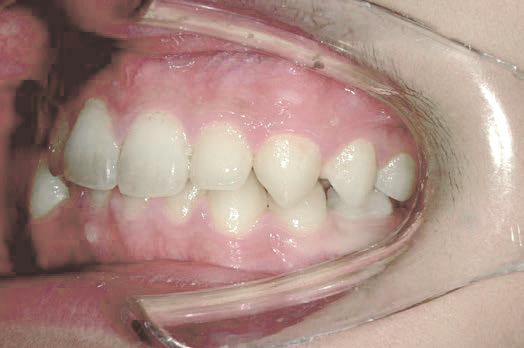

ガタガタな歯並びに悩むも…抜かずに治す選択

Kさん (矯正開始時:8歳)

Before

After

前歯のすき間や歯並びの乱れが見られ、普段の生活の中で、無意識に舌を押しつけるクセや飲み込み方のクセが確認されました。

治療を終えて

装置をしっかり使うことで、あごの位置が整い、舌の正しい位置や動きが戻り、ほっぺたやくちびるの筋肉の使い方も改善されました。その結果、歯並びが整いお口の機能も良くなりました。もちろん非抜歯での治療です。

主訴・治療内容 他院で抜歯のうえ、ブラケット矯正を勧められたが、できれば歯を抜かずに治療したいとの要望で来院されました。

治療期間 5年4ヶ月

費用 495,000円(税込)